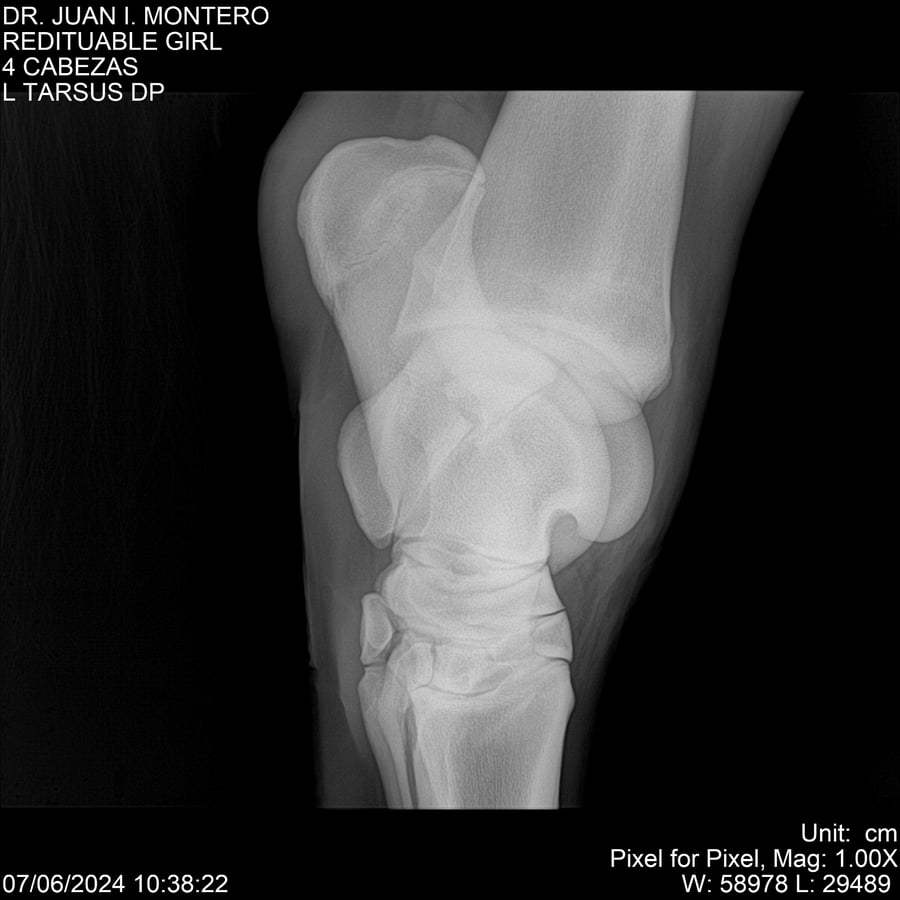

LOTE 19, REDITUABLE GIRL Lote Anterior Volver al remate Lote Siguiente Ficha Contacto Montevideo - Ficha del Lote Identificador: #281096 Categoría: Yeguarizos Montevideo - 79 Visualizaciones ClicData Contacto Empresa: Abelenda N. R., Walter Hugo Nombre*: Teléfono* : E-mail* : Mensaje Enviar Registrese gratis Este contenido Exclusivo está disponible sólo para usuarios registrados Ingresar